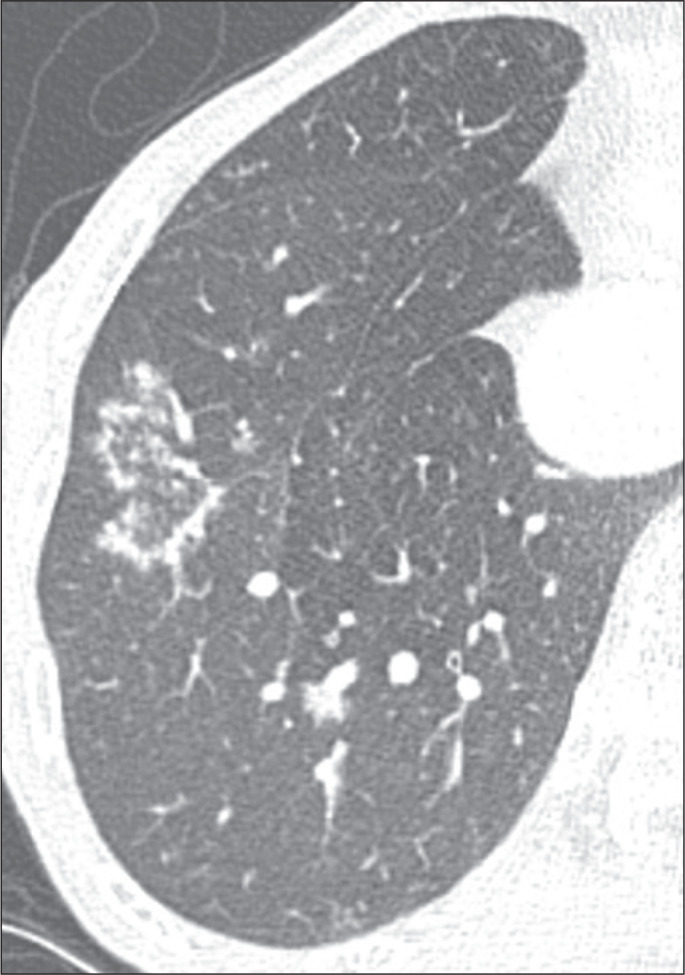

Objective: To characterize the main causes of the reversed halo sign (RHS) on computed tomography (CT) of the chest and its imaging features.

Materials and methods: This was a retrospective study reviewing all chest CT scans for which the report contained the term "reversed halo sign" among those performed between 2015 and 2020 at a tertiary care hospital.

Results: A total of 286 cases were identified, and the corresponding CT images and clinical data were reviewed. In this population, the most common cause of an RHS was pulmonary infarction (in 42%), followed by cryptogenic organizing pneumonia (in 17%) and bacterial pneumonia (in 16%). In addition, the CT characteristics of the RHS were identified in various conditions, such as pulmonary thromboembolism with pulmonary infarction, in which the RHS was typically smooth-walled and solitary with a peripheral distribution.

Conclusion: The RHS can be observed in many contexts, and its CT characteristics, in combination with the clinical picture, can help narrow the differential diagnosis.